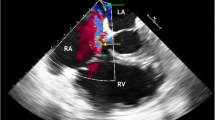

Right internal jugular Avalon cannulas are inserted 31 cm into the central vascular system using the Seldinger technique, percutaneously placed in the vessel using a guidewire and serial dilations under fluoroscopic and/or echocardiographic insertion guidance [18] (Fig. 1). The catheter traverses the superior vena cava, right atrium, with the tip placed in the inferior vena cava. Venous drainage ports positioned in the superior and inferior vena cava draw blood to supply the oxygenator. After gas exchange, the blood is returned to the infusion lumen of the catheter, terminating at a port directed toward the tricuspid valve that delivers a jet of arterialized blood to the right heart (Fig. 2). Insertion of the OriGen DLC is also percutaneous into the right IJ vein, but the tip of the cannula is inserted into the RA. Likewise, the 18 and 22 Fr. NovaPort twin DLCs are inserted 17 cm via the IJ vein into the RA. The largest NovaPort twin 24 Fr. DLC is inserted into the femoral vessel.